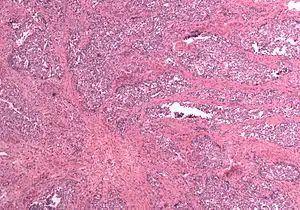

Carcinosarcoma of the uterus

In gross appearance, MMMTs are fleshier than adenocarcinomas, may be bulky and polypoid, and sometimes protrude through the cervical os. On histology, the tumors consist of adenocarcinoma (endometrioid, serous or clear cell) mixed with the malignant mesenchymal (sarcoma) elements; alternatively, the tumor may contain two distinct and separate epithelial and mesenchymal components. Sarcomatous components may also mimic extrauterine tissues (e.g., striated muscle, cartilage, adipose tissue, and bone). Metastases usually contain only epithelial components.